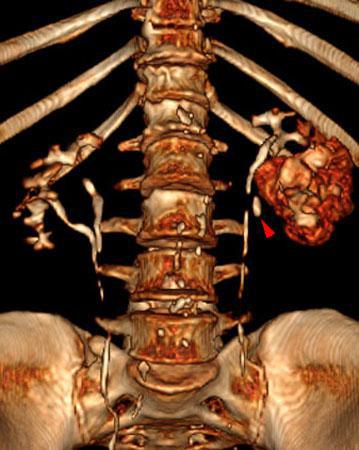

Obstrucción renal en duplicidad. Absceso renal